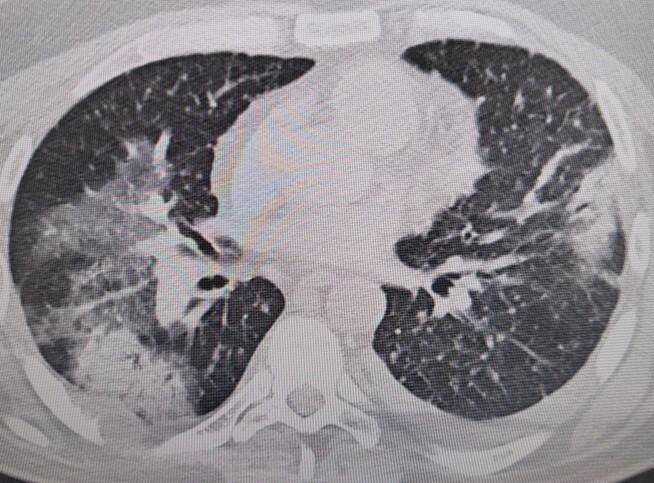

Klimaya bağlı “yaz zatürresine” dikkat